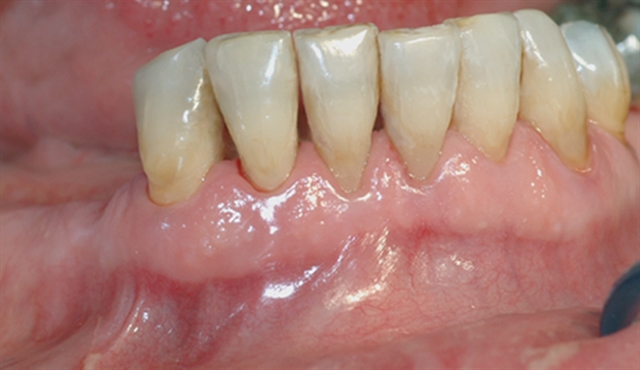

Bildet viser tilsynelatende normale tannkjøttsforhold ved tenner i underkjeven.

• perio stor 2

perio stor 2